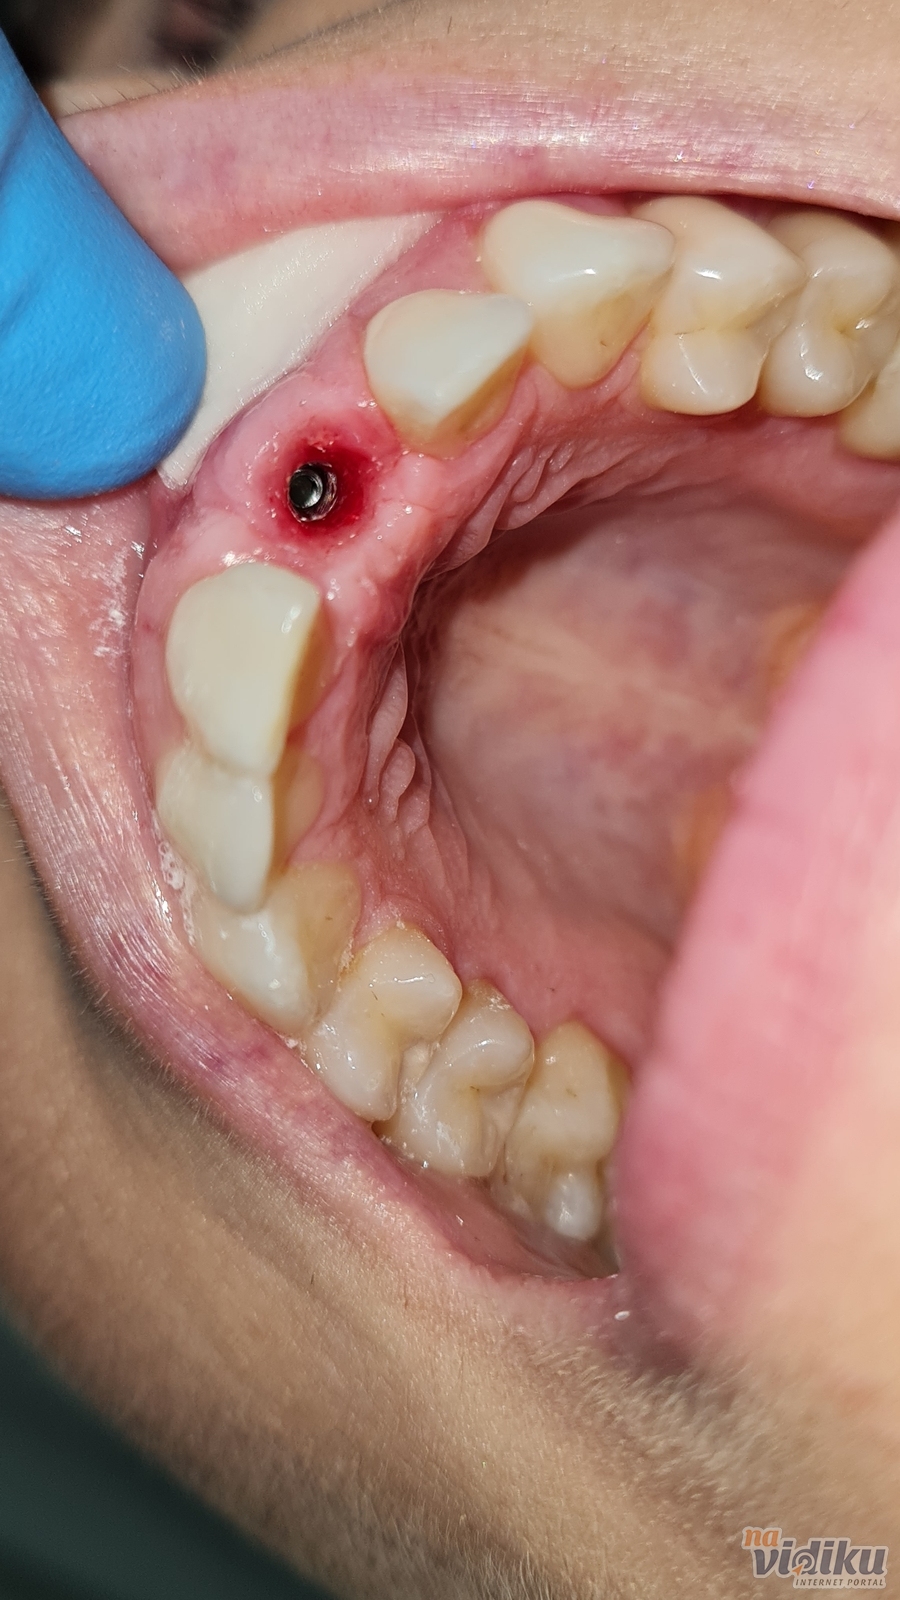

Zub izvađen zbog postojanja ciste na korenu zuba. Ugrađen implant, nakon šest meseci izrađena cirkon krunica.

550e Zimmer implant+ 300e krunica